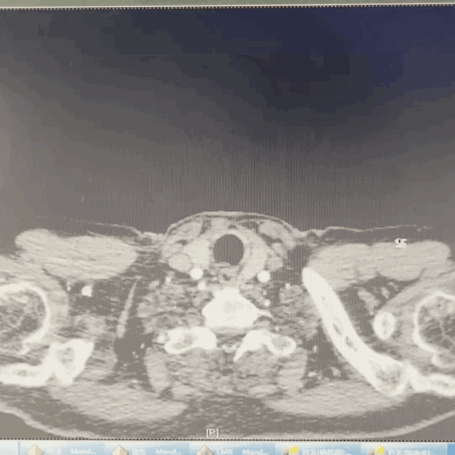

术前CTA详解:

主动脉弓穿透性溃疡,病变大小分别约11*11mm、5*9mm;左颈总动脉后缘处主动脉直径32mm,左锁骨下动脉前缘处主动脉直径29mm,左颈总动脉后缘距离左锁骨下动脉前缘8mm,左颈总动脉后缘距离穿透性溃疡近端7mm。